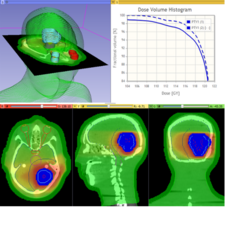

SlicerRT

Qualitative and quantitative comparison of two RT dose distributions

Dose accumulation for adaptive radiation therapy

- Tutorial presentation: pptx pdf

- Dataset: download from MIDAS

- Authors: Csaba Pinter, Andras Lasso, Queen's